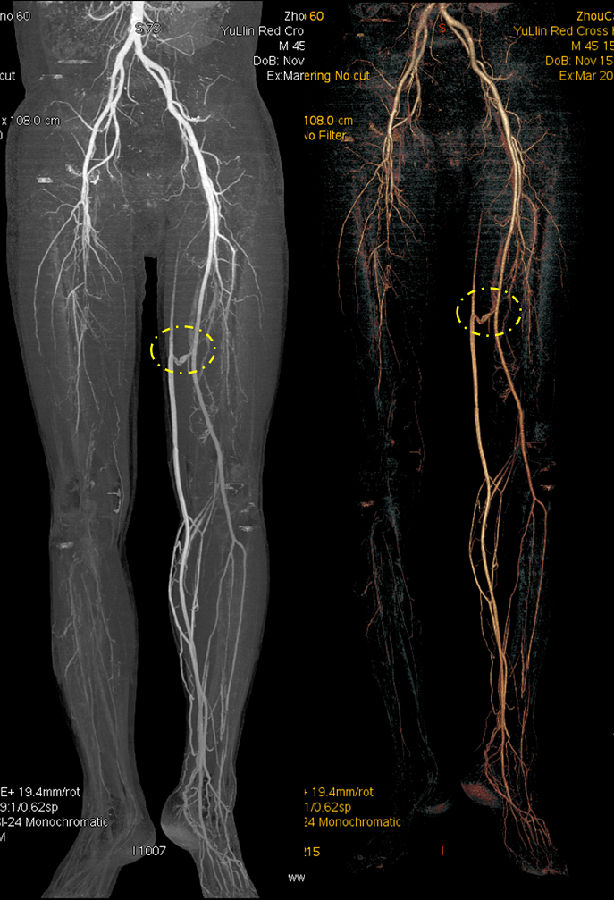

病史 M,45Y 病人主诉:反复右足趾疼痛麻木4月,右足背肿痛4天 临床诊断:糖尿病

CT表现: 右侧股动脉栓塞

动静脉瘘

病例点评及临床价值: 常规下肢CTA对糖尿病足下肢各级动脉病变的诊断价值是目前公认的经济、准确的方法。CTA检查可以准确显示下肢动脉病变部位及程度,对糖尿病足提供综合治疗方案,可显著降低患者的病残率。

常规CTA对诊断糖尿病足患者下肢膝上及膝下动脉狭窄≥50%的可靠性高,而预测足动脉闭塞的灵敏度相对较低;即使提高造影剂浓度、总量及注射流率也无法来满足足部微小动脉显示的需求。

GSI扫描能使用低keV图像满足空间分辨率和密度分辨率兼顾的要求,在常规造影剂注射方案情况下,一次扫描通过调整keV同时满足诊断及微小动脉显示需要。该方法可在临床解剖研究、病变血供发现、血管受侵状况、手术指导及断指再植术后评估等方面有重要作用。